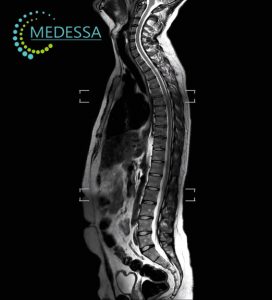

МРТ-діагностика в медичному центрі MEDESSA